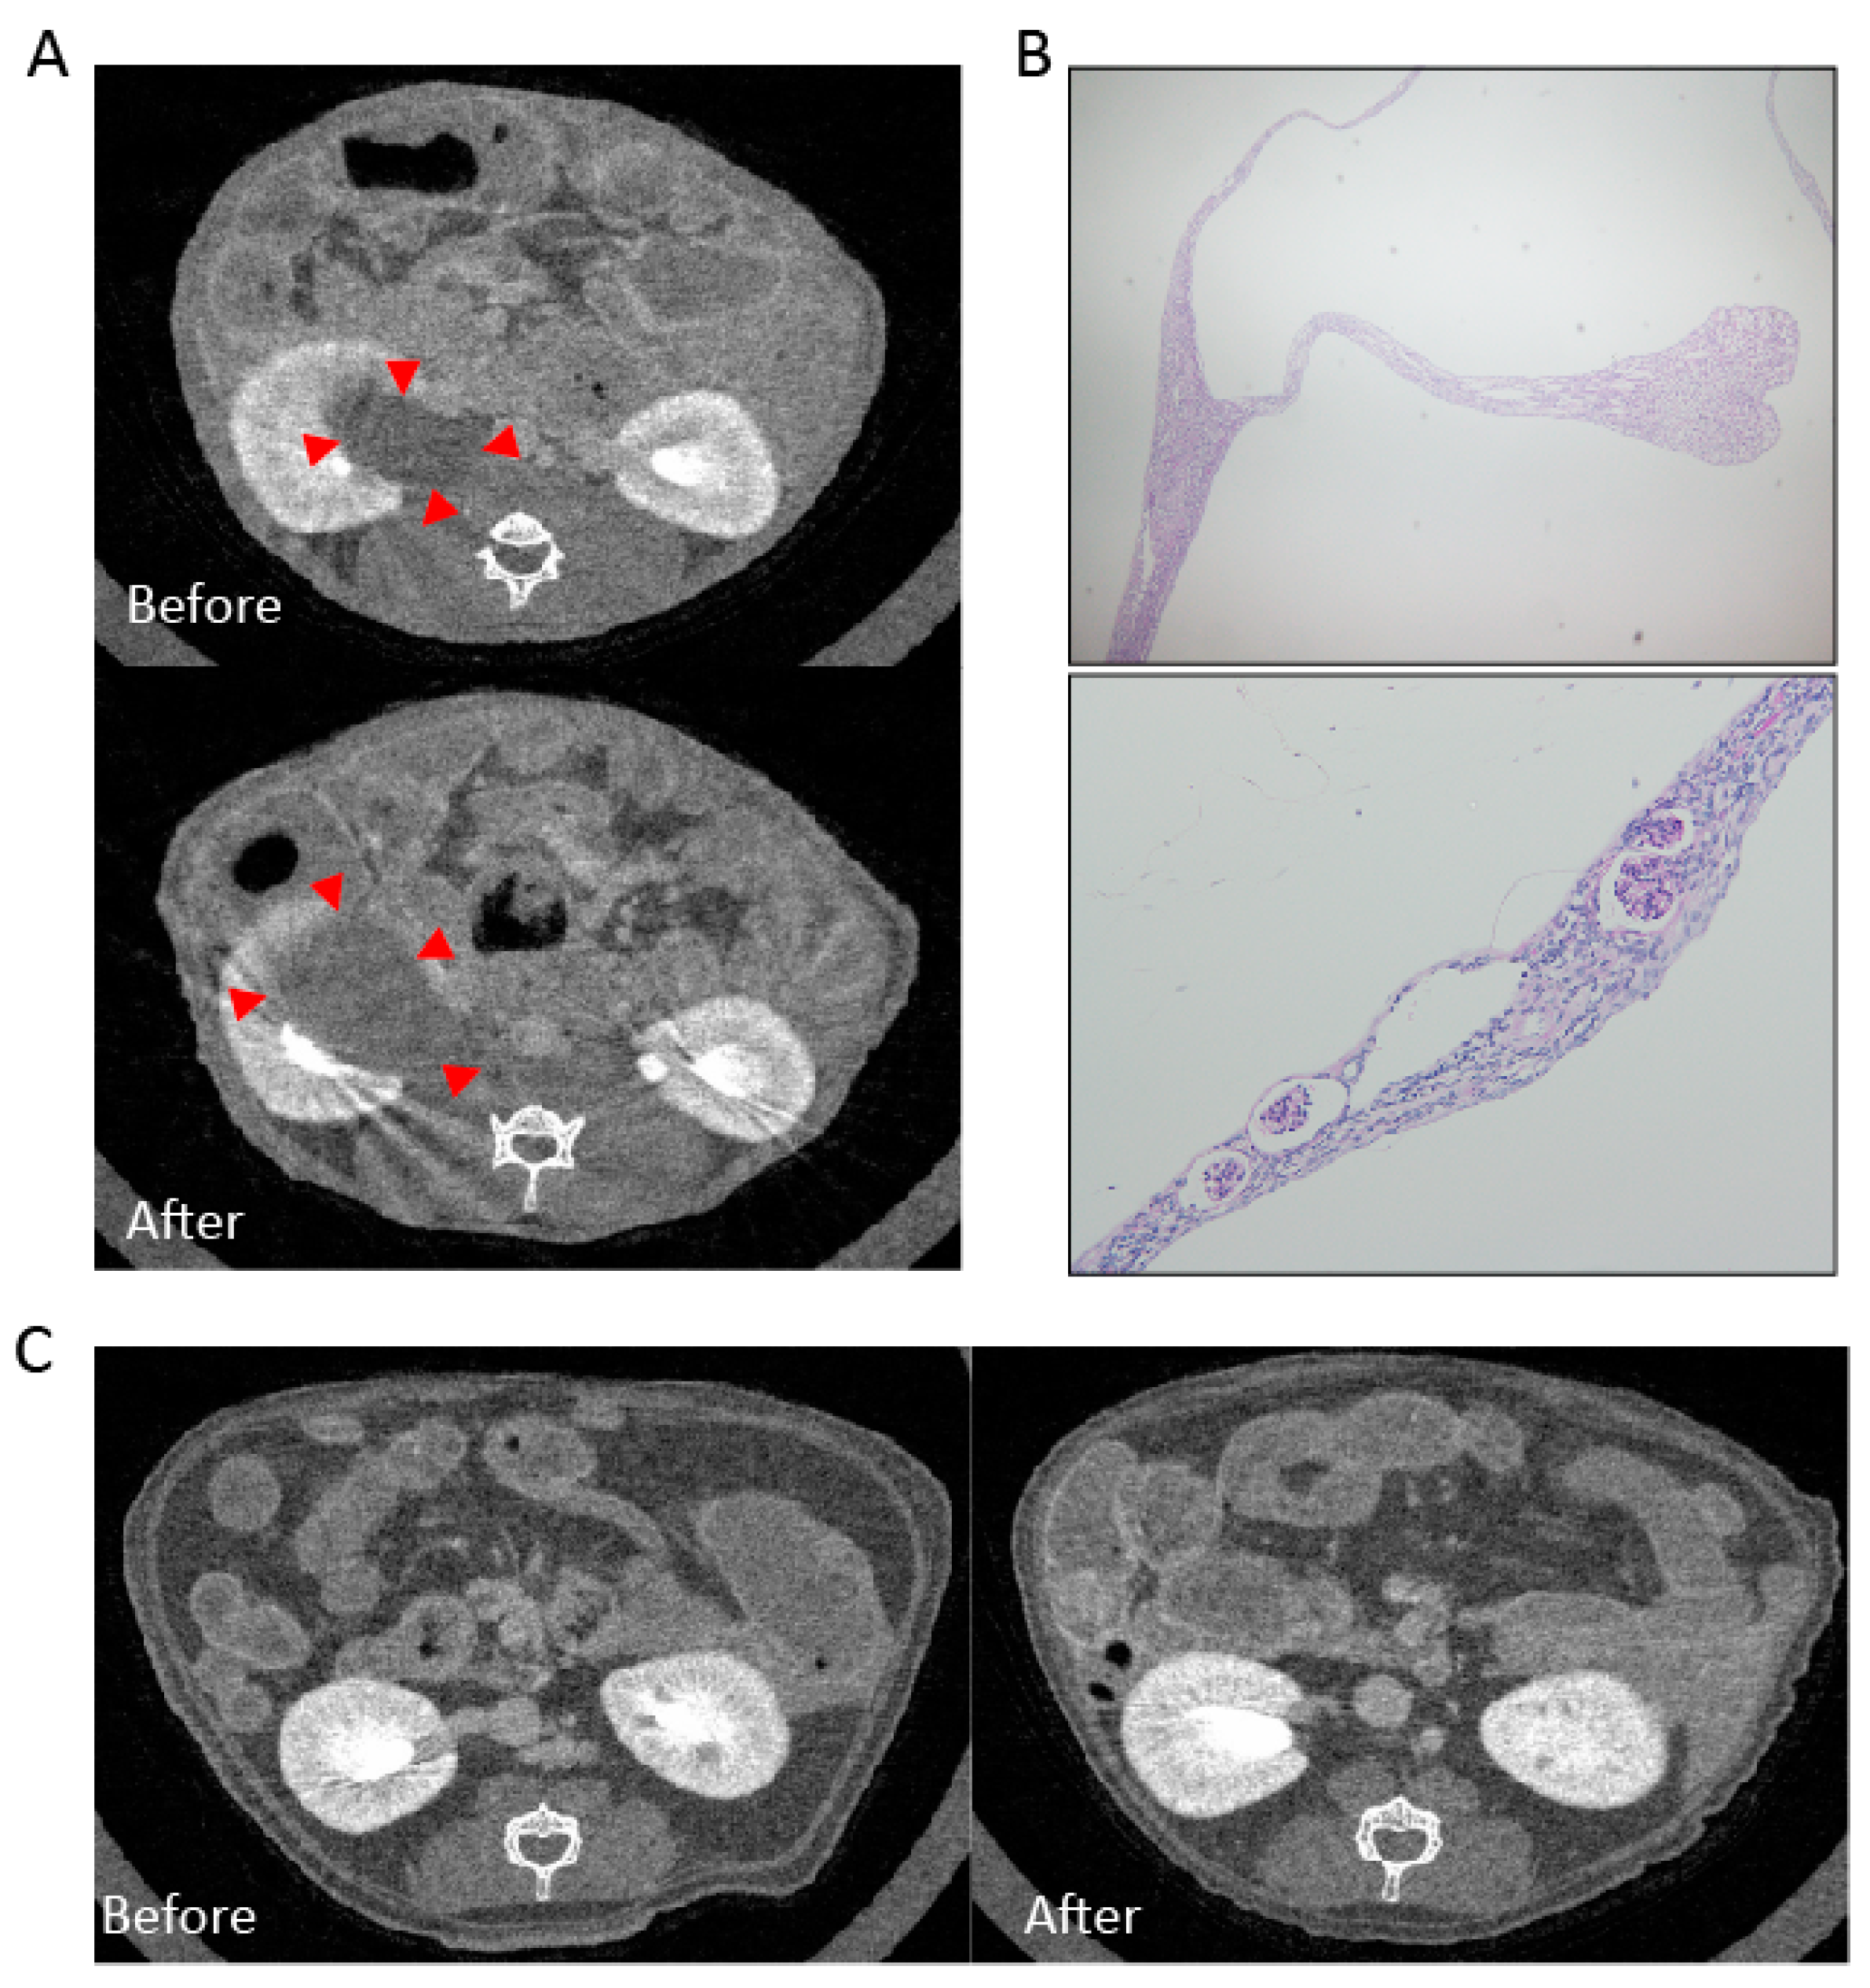

2.1. Case Report

2.2. Experimental Animal Model

2.2.1. Mesangial Expansion in Crizotinib-Treated Mouse

2.2.2. Crizotinib Caused Renal Histopathological Changes